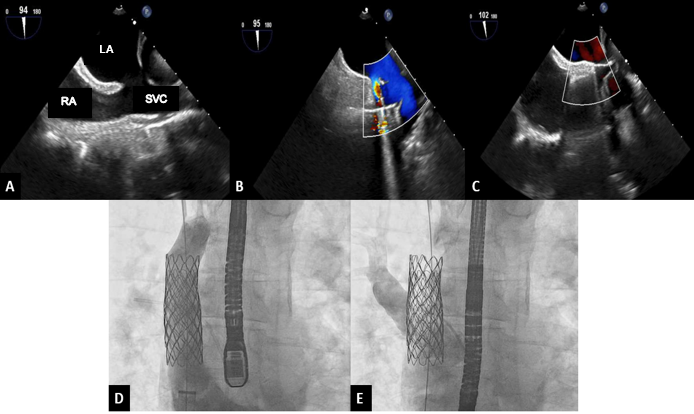

Given the right ventricular dilation shown in the TTE, a cardiac MRI was performed. The MRI showed moderate RV dilation with evidence of partial anomalous pulmonary venous drainage (PAPVR), with the right upper and middle pulmonary veins draining into the superior vena cava (SVC). There was evidence of significant left-to-right shunt with a Qp/Qs of 1.8. Cardiac computed tomography angiogram (CTA) showed a large superior sinus venosus atrial septal defect (SVASD) between the wall of the SVC, and the right middle pulmonary vein measuring 2.6 cm in the superior-inferior dimension and 1.7 cm in the right-left dimension. Right upper and middle pulmonary veins drained into the SVC just above the defect (Figure 1, Video 1). There was normal drainage of the remaining pulmonary veins.

Upon review of the CTA, the defect appeared amenable to percutaneous closure with a covered stent in the SVC. The patient was counseled on options for closure, including surgical repair and a covered stent. Intraoperative TTE again showed the SVASD and anomalous pulmonary venous drainage. Two covered stents were placed; the first stent successfully routed the anomalous veins posteriorly across the defect to the left atrium without pulmonary venous obstruction (Video 2). There was a small residual ASD (4 mm) at the inferior portion of the stent, for which a second stent was placed. There was no residual left-to-right flow after the second stent and no pulmonary venous obstruction (Figure 2; Videos 3 and 4). At 1-month follow-up, the patient was asymptomatic and TTE demonstrated a significant decrease in right ventricular size.